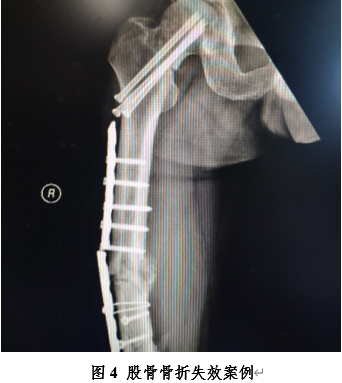

其实,力学是一门交叉研究突出的学科。除了人们熟知的建筑、机械、航空、航天等领域,力学在生命科学领域也发挥着重要的作用。例如,骨科手术中经常使用钢板对骨折进行内固定(图4),这样就需要钢板和钉子等有足够的强度,以保证在骨折完全愈合并能够承重前,由钢板/钉子来承受骨折部位的外力。实际中,由于骨骼是一种生物材料,在力学性能上和金属材料存在较大差异,因此由骨骼和钢板/钉子组成的耦合结构受力情况远比建筑物的杆件结构复杂得多。主要体现在以下两点:其一,骨骼和钉子之间的接触导致骨受损、螺钉松动等问题,因为两种不同材料在接触面会产生微观尺度的挤压、划擦等;其二,由于钢板/钉子的介入改变了骨骼原先的受力状态,导致应力遮挡,从而引起某些部位骨生物结构发生负面变化,或者说破坏了原有正常生物结构。上述问题都会导致手术失败的风险,给患者带来更大的痛苦。所以骨科大夫要懂得一定的力学知识。